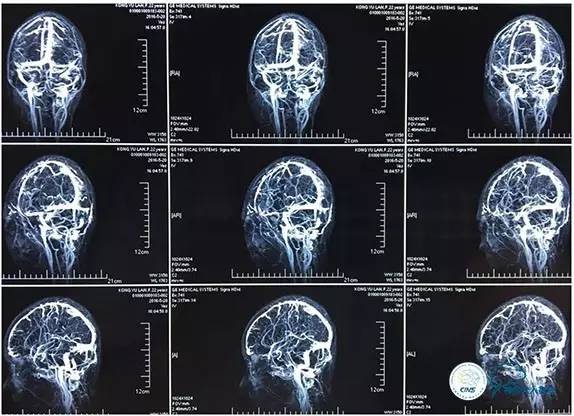

MRV

术中造影

5ml/s,总量8ml,压力100~150

术后造影

术毕远近端压力差为:0

右侧ICA造影正侧位

右侧ICA造影斜位

右侧ICA正侧位

右侧ICA斜位

静脉淤滞

左侧ICA斜位

左侧VA正斜位

狭窄较前有改善

术中右侧ICA造影

右侧ICA斜位及窦内造影

窦内造影及路图

术后右侧ICA造影

术后右侧ICA斜位